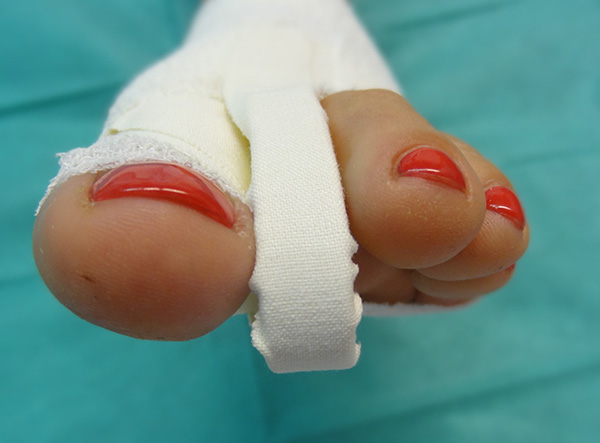

Sämtliche Operationsschritte werden über kleine Stichinzisionen durch die Haut durchgeführt. Isham beschrieb das Verfahren ohne Osteosynthese. Da es sich bei den knöchernen Korrekturen um mediale Closing wedge Osteotomien handelt, werden diese anschließend durch spezielle Zügelverbände (Tape) in Position gehalten. Postoperativ ist eine sofortige Vollbelastung im flachen Verbandsschuh möglich, der Wechsel auf Konfektionsschuhe erfolgt meist nach 4 bis 5 Wochen.

• Verbandmaterial zum Anlegen eines Redressionsverbandes (sterile Kompressen, sterile Watte, Haftbinde, Tape).

Postoperative Behandlung

• Verbandswechsel (vom Operateur selbst) 7, 14, 21 und 28 Tage postoperativ mit Freigabe nach 4-6 Wochen.